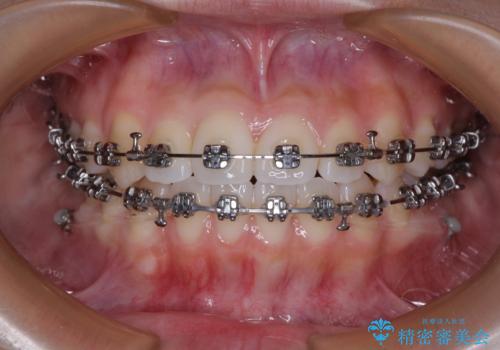

- 矯正装置

- メタルブラケット

マウスピース矯正での自己管理の煩わしさが気になる方には、ワイヤー矯正がおすすめです。